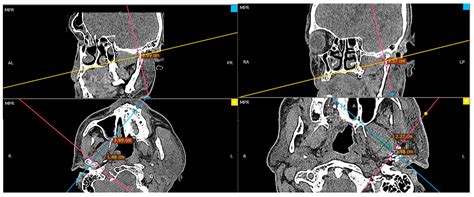

Radiological Identification

In modern medicine, identifying the medial pterygoid plate through imaging—such as Computed Tomography (CT) or Cone Beam CT (CBCT)—is essential for diagnosing anatomical variations or pathologies. Because the bone is relatively thin, high-resolution imaging is required to visualize it clearly, especially when assessing for fractures or developmental anomalies of the skull base.

💡 Note: Use multiplanar reconstruction (MPR) in CBCT software to accurately view the coronal and axial cross-sections of the pterygoid process for better diagnostic precision.